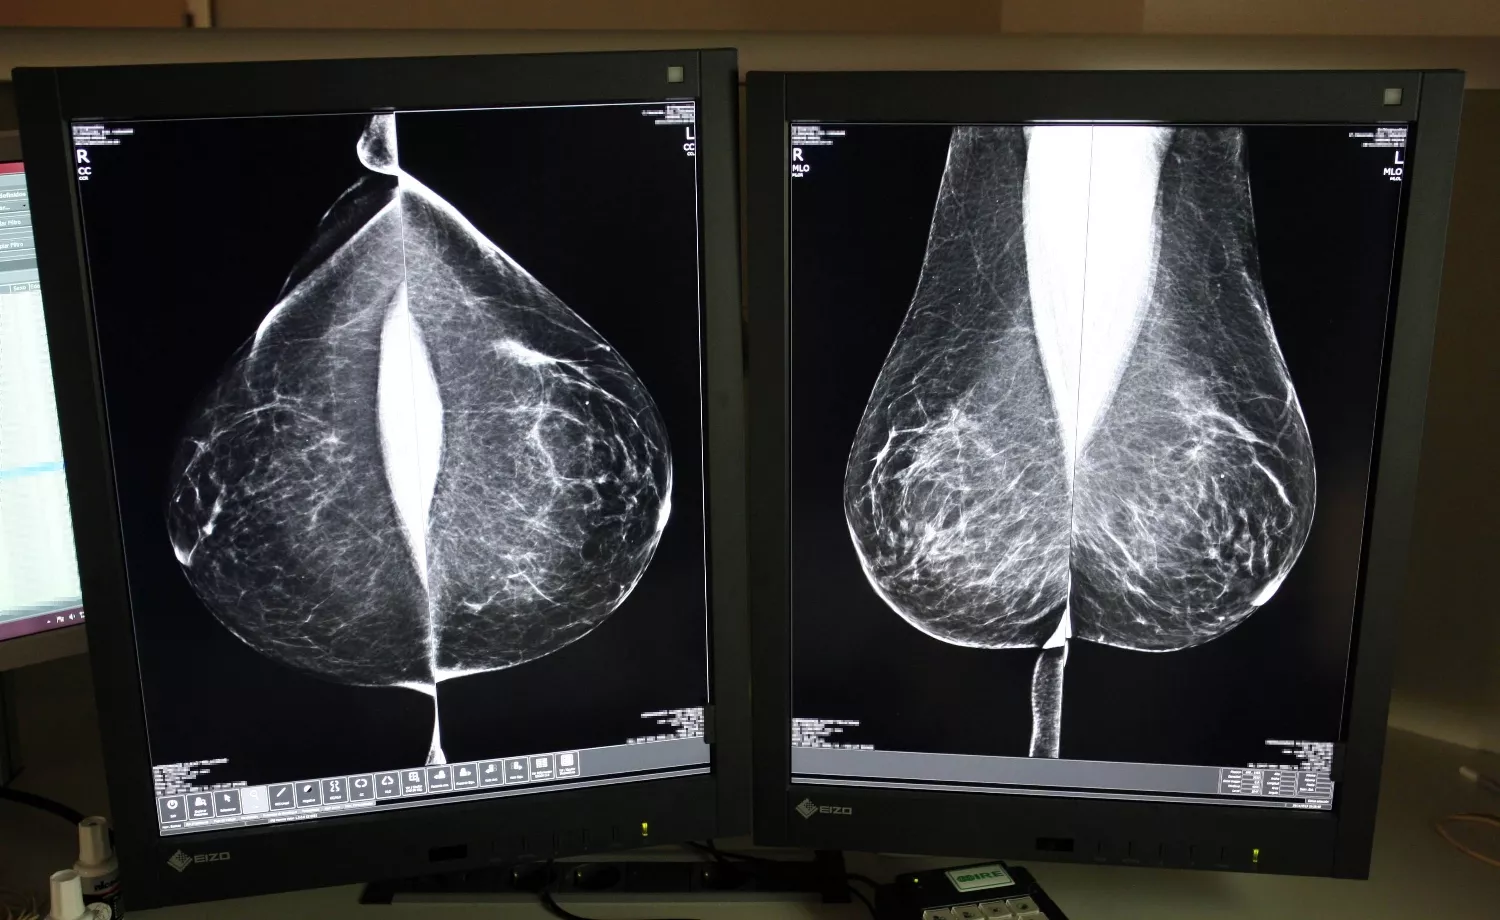

Diversos estudios científicos demuestran que la inteligencia artificial se ha convertido en un aliado de los radiólogos, con un alto rendimiento en los cribados, que pueden ayudar a evaluar, en el caso del cáncer de mama, las mamografías de bajo riesgo, como también en la detección temprana de esta enfermedad, siempre como una técnica de apoyo en la toma de decisiones. Incluso, algunos ensayos indican que la inteligencia artificial es capaz de predecir el riesgo de desarrollar cáncer de mama cinco años antes de que aparezca. En concreto estas conclusiones se extraen de un modelo desarrollado por el Instituto de Tecnología de Massachusetts, que se ha probado en varios países. No obstante, los expertos coinciden en la necesidad se seguir trabajando en más estudios y ensayos prospectivos.

También, coinciden en que ayuda a la lectura, lo agiliza y puede ayudar, también, ante la falta de radiólogos. En Castilla y León el programa de de detección precoz de cáncer de mama establece un sistema de doble lectura, que implica que pasen por manos de al menos dos radiólogos. El año pasado, la Junta optó por externalizar este servicio, práctica común en el conjunto del Sistema Nacional de Salud, con el fin de agilizar la lectura de 125.000 pruebas anuales y también después de que se ampliara el rango de edad hasta los 74 años de edad. Invirtió casi cuatro millones de euros, a los que podrían sumarse este año otros 3,3 millones, con un nuevo contrato.